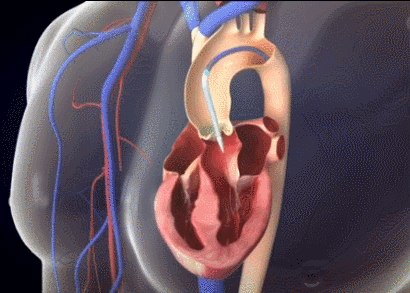

厦心急诊科主任王斌介绍,心脏血液进出有4个重要的阀门,都是瓣膜结构,其中就包括主动脉瓣和二尖瓣。心脏的血液经由主动脉瓣泵入主动脉,进而随着血管分支遍布全身。4个阀门中,主动脉瓣承受的压力最大,因而,主动脉瓣虽然耐用,但长年承受巨大压力还是容易坏掉。主动脉一旦狭窄,心脏的血液就无法顺利泵入主动脉供给全身,将造成严重后果。

如何能更精准有效地将人工瓣膜微创植入主动脉瓣,且不影响二尖瓣机械瓣的运作呢?厦心王焱院长率团队进行了多次缜密术前讨论,最后决定为陈奶奶采用刚刚上市不久的新型人工瓣膜——可回收Venus A-Plus瓣膜。作为我国首个可回收瓣膜系统,该瓣膜能有效降低复杂手术难度,一旦瓣膜植入位置不合适,还可以回收后再次尝试,让医生在术中能更从容地进行精准定位释放,减少严重并发症的发生,从而降低手术风险,提高成功率。